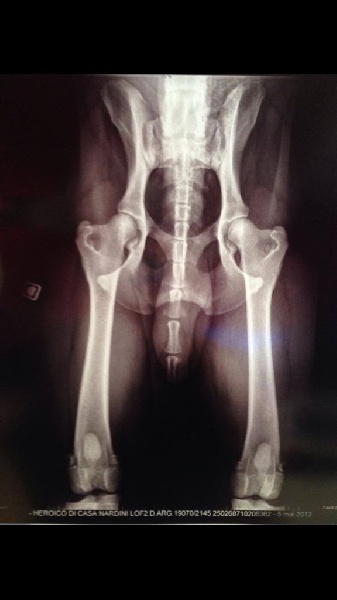

Radio dysplasie parfaite 07/08/2014

Heroïco 27 mois 43kg indemne dysplasie.